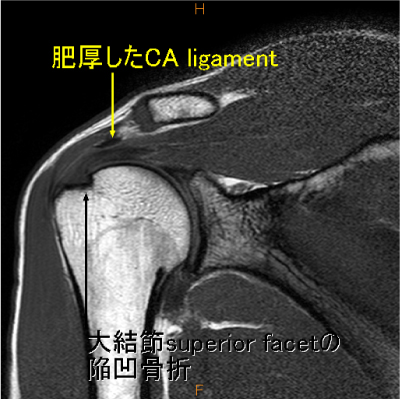

棘上筋腱停止部関節側に剥離を認めており、同部大結節に陥凹が存在する。

後上方関節唇損傷+ガングリオン、棘上筋腱停止部関節側剥離